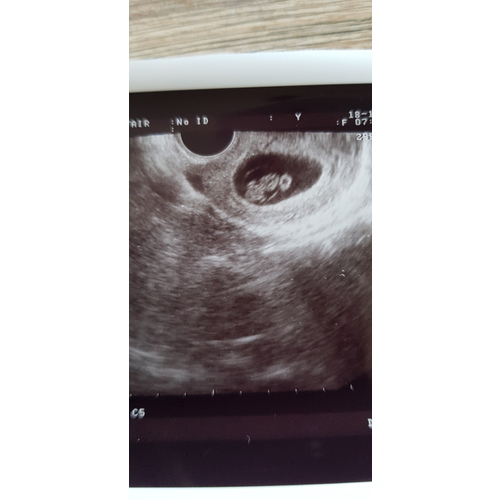

Ik heb er twee gehad in dezelfde week. Eentje was een 3d echo en eentje een 2d bij de gynaecoloog. Ik vond dit buiten beetje oncomfortabel na een tijdje geen probleem. Vooral met de 3d echo lag ik er echt een halfuur. De echo's waren gemaakt met 8 weken.

Vorige week een echo gehad met 6 weken zwangerschap en een mooi kloppend hartje gezien😍